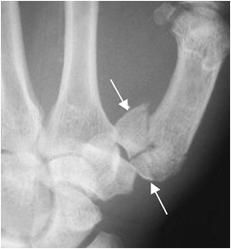

Fig 59 D. Luxofractura de Rolando.

Rx AP. Luxofractura conminuta en la articulación carpometacarpiana del pulgar, por lesión de Rolando.